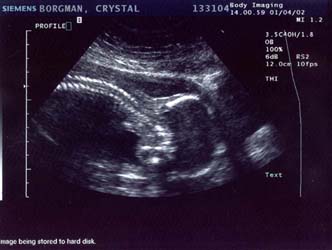

1/4/02

20 weeks

Well

it's a stubborn little bugger. The ultrasound technician

tried and tried so hard to find out the sex, bless her

heart. At the beginning she thought maybe she saw something

that would indicate it was a boy, but she wasn't even

remotely sure by any means. She said she'd check again

later and wasn't confident in the least bit that it was

actually a boy.

Later came, and

went. Baby had its legs crossed the whole time. She

also said there was a lot of umbilical cord around the

legs, so what she saw earlier may have been the cord

too. I drank a full 12 ounces of Coke before I went

in, hoping that would get the baby moving. It was moving

alright, but apparently not enough. The tech tried pushing

on my belly at all angles to get the baby to move but

it would not budge. Well I have to say I'm pretty bummed.

I've been holding out on buying clothing and stuff...

but now I know what I need to get: a whole shit-load

of gender neutral stuff. No, we will not be getting

another ultrasound so this is it until the baby's born.

On a happier note,

everything checks out ok. We saw 4 chambers in the heart

and it was beating away happily at about 142 bpm, she

said. All organs appeared to be present and looking

good. The big shocker was that the estimated weight

was 1 pound, 11 ounces. OUCH! All my pregnancy calendars

say it should still be under a pound... but maybe their

estimate was off. That does, however, help explain my

6-pound weight gain in the last month. At any rate,

all the measurements were normal and my due date remains

unchanged.

Ultrasound Pictures:

Profile with head

on the right, facing down (towards my back), spine clearly

visible

Large

- 663x550 pixels / 66.1K

Small

- 332x250 pixels / 28.2K

Leg (foot is on

the right, pointing up)

- 682x500 pixels / 68K

- 341x250 pixels / 28.8K